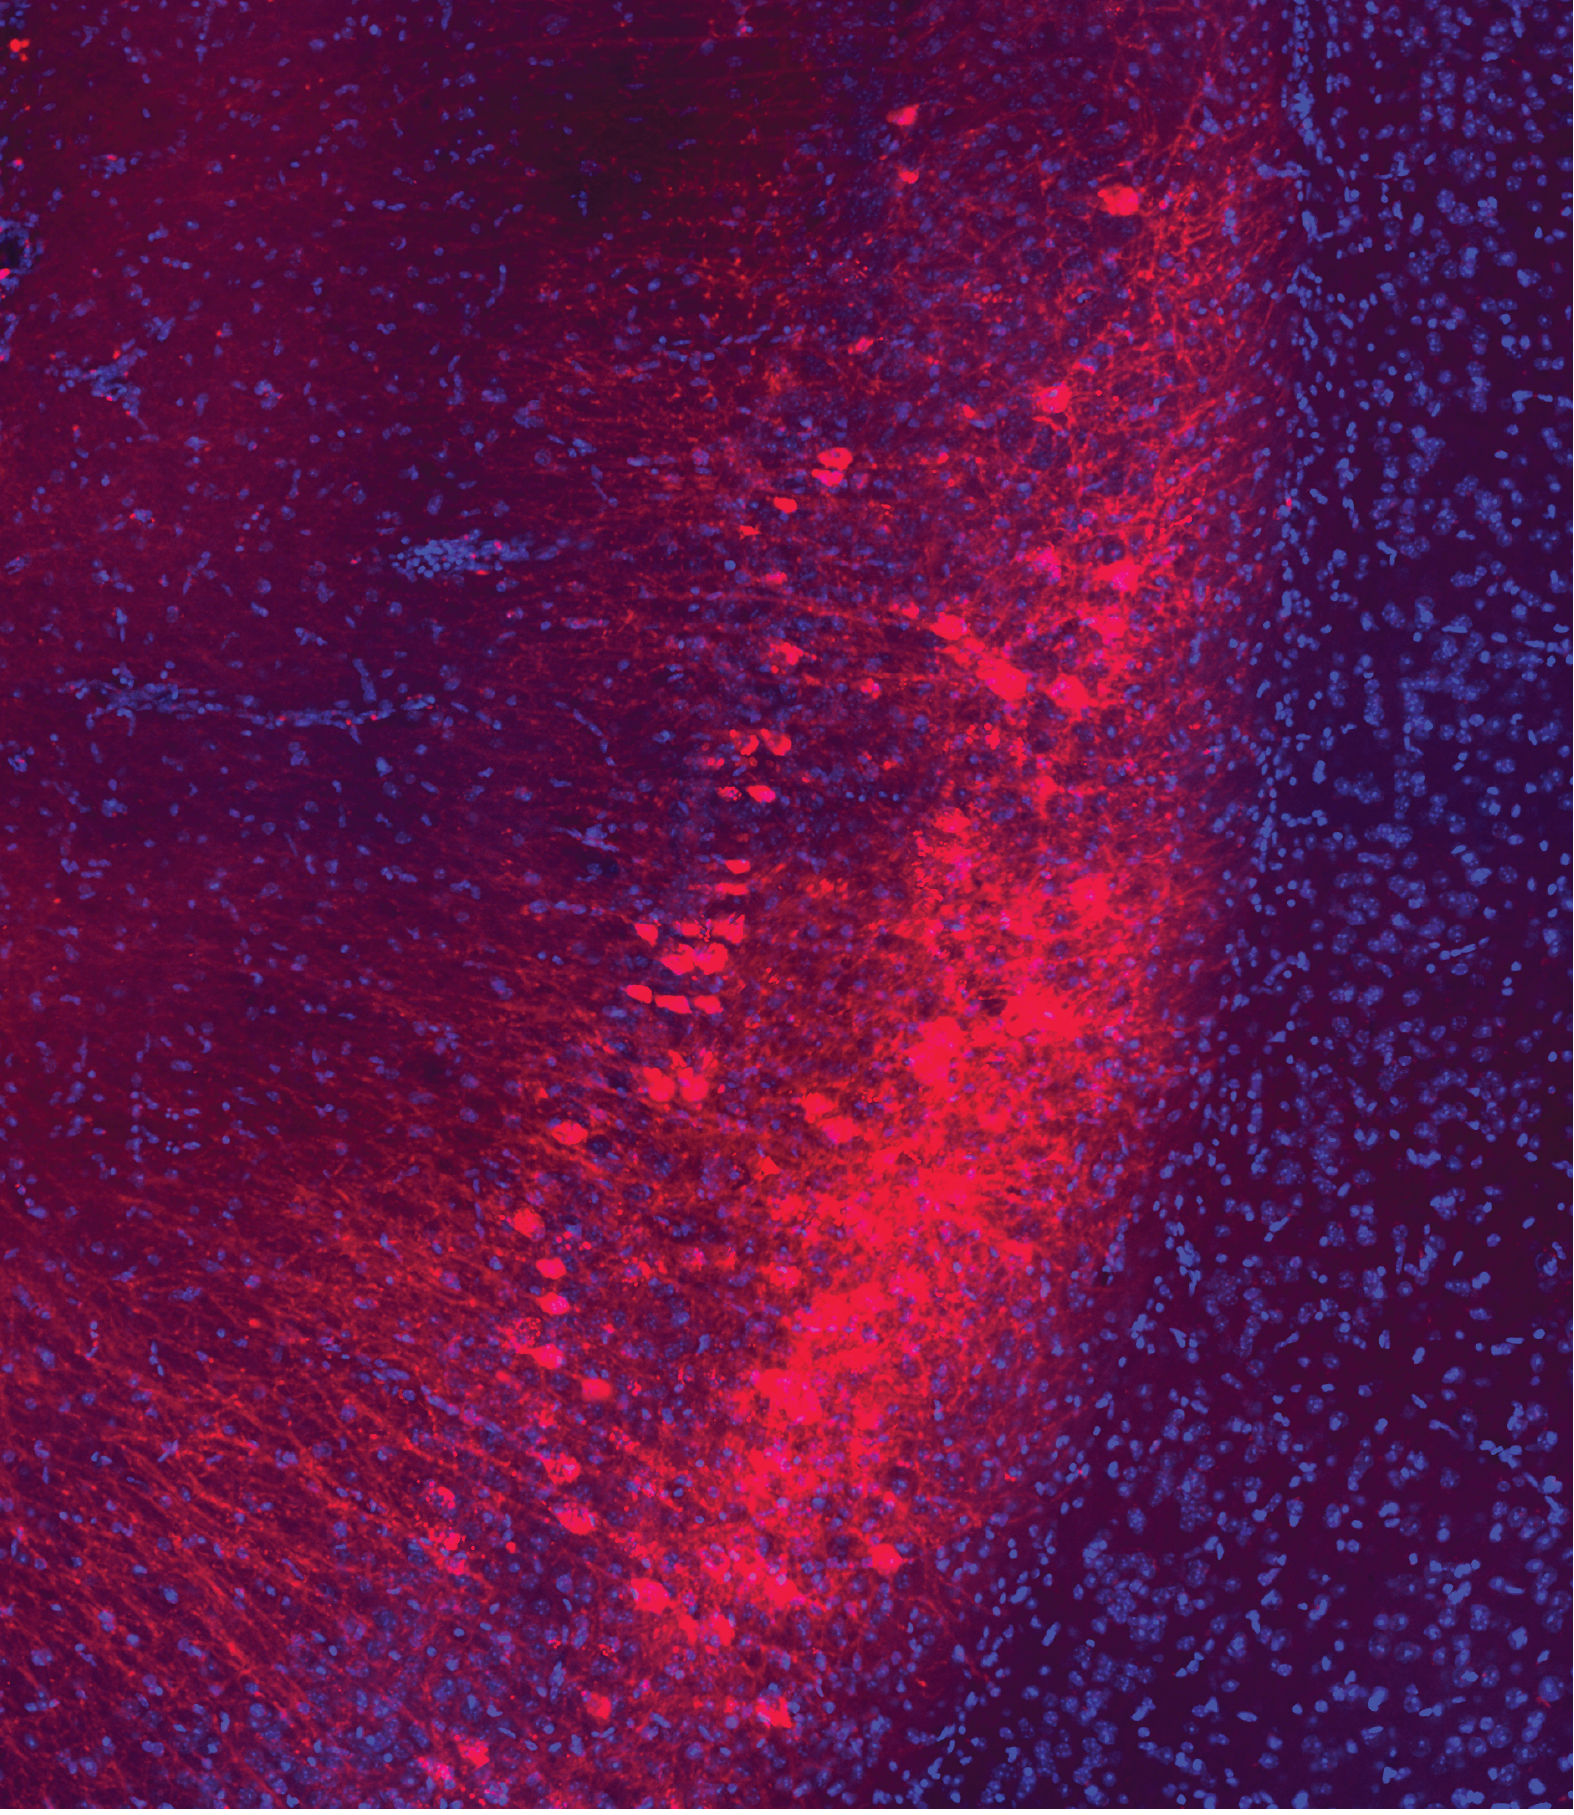

Representative image of BLA-projecting vCA1 neurons transfected with hM3Dq–mCherry (observed in all 25 mice). Scale bar, 100 μm.